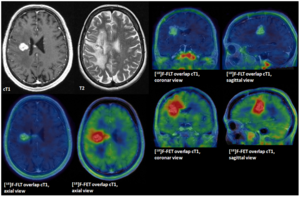

- 4.30 An Intra-Individual Comparison of MRI, [18F]-FET and [18F]-FLT PET in Patients with High-Grade Gliomas

- 4.31 The Swallow Tail Appearance of the Healthy Nigrosome – A New Accurate Test of Parkinson’s Disease: A Case- Control and Retrospective Cross-Sectional MRI Study at 3T